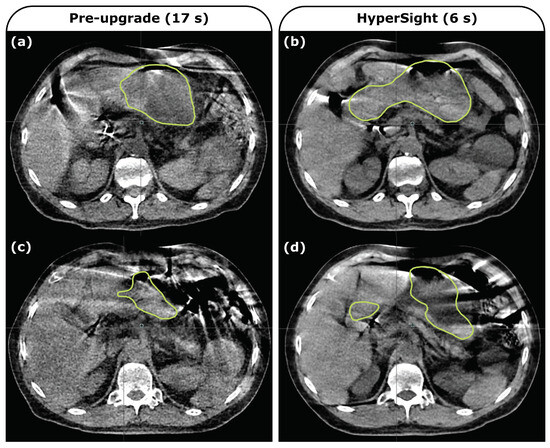

Figure 5.

Daily CBCT images from a single patient (not included in the 10 patient cohort of this study) acquired using the pre-upgrade imaging panel with a 17 s acquisition period (left) and using the upgraded HyperSight system with a 6 s acquisition period (right). Ethos-produced stomach contours at a representative slice are shown. The anatomy observed in fractions (a,b) is similar but the full extent of the stomach is more accurately contoured in the post-upgrade image (b). Motion artifacts that lead to poor contouring performance as illustrated in pre-upgrade image (c) also cause failures post-upgrade (d).